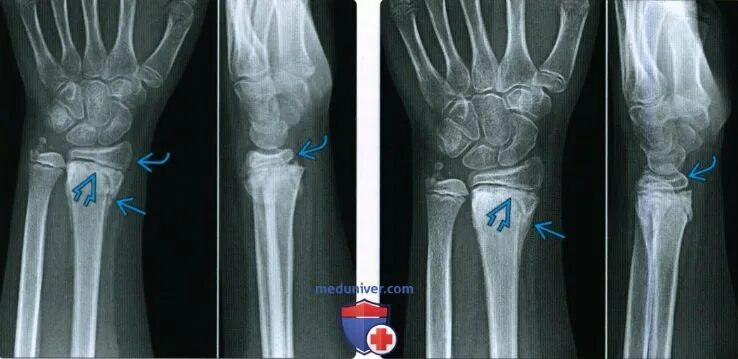

Чтобы быстрее сросся перелом руки